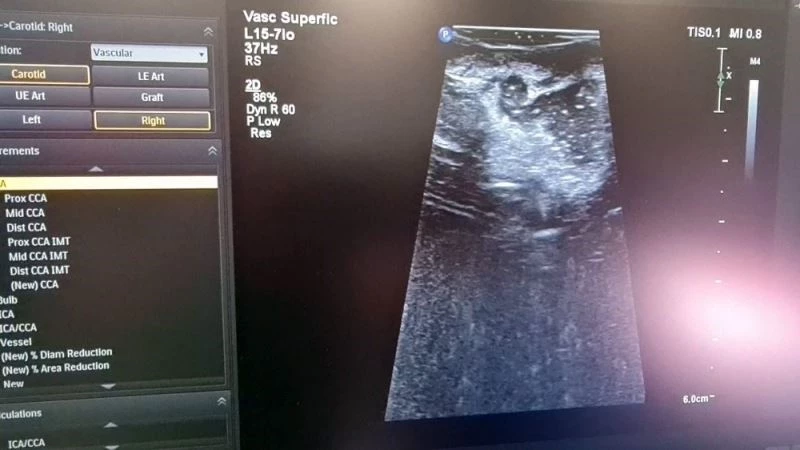

Cumhurbaşkanı Recep Tayyip Erdoğan’ın Başakşehir Çam ve Sakura Hastanesinin açılışında canlı olarak bağlandığı ve içerisinde İntraoperatif MR bulunan Hibrit Ameliyathane de ilk ameliyat geçtiğimiz gün gerçekleştirildi. Kamu Hastaneleri arasında ilk olma özelliği taşıyan bu ameliyathane de hastanın ameliyatının tamamlandığı düşünüldüğünde hasta ameliyathane içerisinde bulunan MR odasına alınıyor ve burada hastaya son kez bir MR çekiliyor. Çünkü ameliyatlar esnasında mikroskopla ameliyat yapılsa bile bazı durumlar da çok küçük de olsa tümör dokuları kalabiliyor. Bu yöntemle hasta ameliyattan çıkarılmadan bu tespit ediliyor ve ikinci bir ameliyata gerek kalmıyor.

Ameliyathane de ilk ameliyat 27 yaşında beyninde tümör olan bir hastaya gerçekleştirildi. Uzun bir ameliyatın ardından hastanın ameliyatının tamamlandığı düşünüldü. Ancak ameliyatı gerçekleştiren Doç. Dr. Ömür Günaldı hastanın MR’ının çekilmesini istedi. Çekilen MR’da gözle ve ultrasonla görülmesi imkansız olan küçük bir tümör dokusunun kaldığı fark edildi. Hasta tekrar ameliyathaneye alındı ve ameliyata devam edilerek hasta da bulunan son parça da alınarak hastanın ameliyatı tamamlandı.

Kullanılan bu yöntemle hem hastanın hem de hekimlerin konforunun arttığını belirten Beyin Cerrahi Kliniği Eğitim Sorumlusu Doç. Dr. Bekir Tuğcu, “Yaptığımız bu ameliyatta kullandığımız yöntem bizim cerrahi de son dönemler de kullandığımız teknolojik üstünlüklerden bir tanesi. Bizim genel kuralımız şudur bir cerrahi sırasında cerrahinin sonucunu asıl belirleyen şey daha çok cerrahi ekiptir. Yani cerrahından tutun anestezi uzmanından hemşiresine kadar bu ekibin bir başarısıdır. Ama son dönemler de özellikle beyin cerrahisinde bir takım teknolojik gelişmeler bizim cerrahi sonuçlarımız da daha fazla başarılı olmamızı sağlıyor. Bugün de bununla ilgili bir ameliyatı Başakşehir Çam ve Sakura Hastanemizde ilk defa gerçekleştirdik. Şu anda bir beyin tümörlü hastamız var bu hastamızda gerçekleştirdiğimiz ameliyat sırasında her ne kadar mikroskopla yapsak da ameliyatı tümörlerin sınırlarını bazen normal sınırdan tam olarak ayırt edemiyor olabiliyoruz. Bu tip durumlar da ameliyatta hastadan tümörü tam olarak çıkarttığımızı düşündüğümüzde bile kontrol filmlerinde geriye bir miktar tümör dokusu bıraktığımız hastalar olabiliyordu çünkü bunu ameliyatlar da tam olarak bunu anlamak mümkün değildi. Ama burada olduğu gibi İntraoperatif MR’ınız varsa ameliyat devam ederken hastayı derhal arkamızda bulunan MR odasına hasta uyurken alıyoruz. Yeni bir MR çekiyoruz eğer geride kalan bir tümör dokusu varsa tekrar hastayı masaya geri alarak ameliyata devam ederek o geri kalan dokuyu hastayı uyandırmadan servise almadan almış oluyoruz. Bu hem bizim için hem de hasta için bir konfor. Çünkü ameliyat sırasında daha fazla müdahale etme şansı veriyor bize. Hasta için de konfor bazen bu tip hastalar da ikinci bir ameliyat ihtiyacı olabiliyor ertesi gün veya bir başka gün bunun önüne geçmiş oluyoruz. Bu hastamızda son derece küçük bir tümör dokusu kaldığını fark ettik çektiğimiz MR da bu her hasta da bu kadar küçük bir tümör dokusu kaldı diye tekrar ameliyat edeceksiniz diye bir durum yok bazen ek tedavilerle bazen de sadece takiple bunları devam ettirebiliyoruz. Ama bazı hastalar da bu son derece önemli olabiliyor. Geri kalan yaşam konforu bakımından bu hasta için de öyle tekrar yeniden bu dokuyu almak zorunda kalabilirdik ama bu İntraoperatif MR sayesinde bunu tespit ettik ameliyata devam edeceğiz ve o küçük parçayı da alacağız” diye konuştu.

Bu yöntem ile yapılan ameliyatların çok daha güvenli bir cerrahi sağladığını belirten Beyin Cerrahi Kliniği İdari Sorumlusu Doç. Dr. Ömür Günaldı, “İntraoperatif MR da ilk beyin ameliyatımızı gerçekleştirdik. Önce ultrasonla görüntüledik daha sonra İntraoperatif MR çektirdik. Bu yöntem hasta için daha güvenli bir cerrahi sağlıyor. Bize de ameliyat esnasında sonucu değerlendirme imkanı tanımış oluyor” dedi.